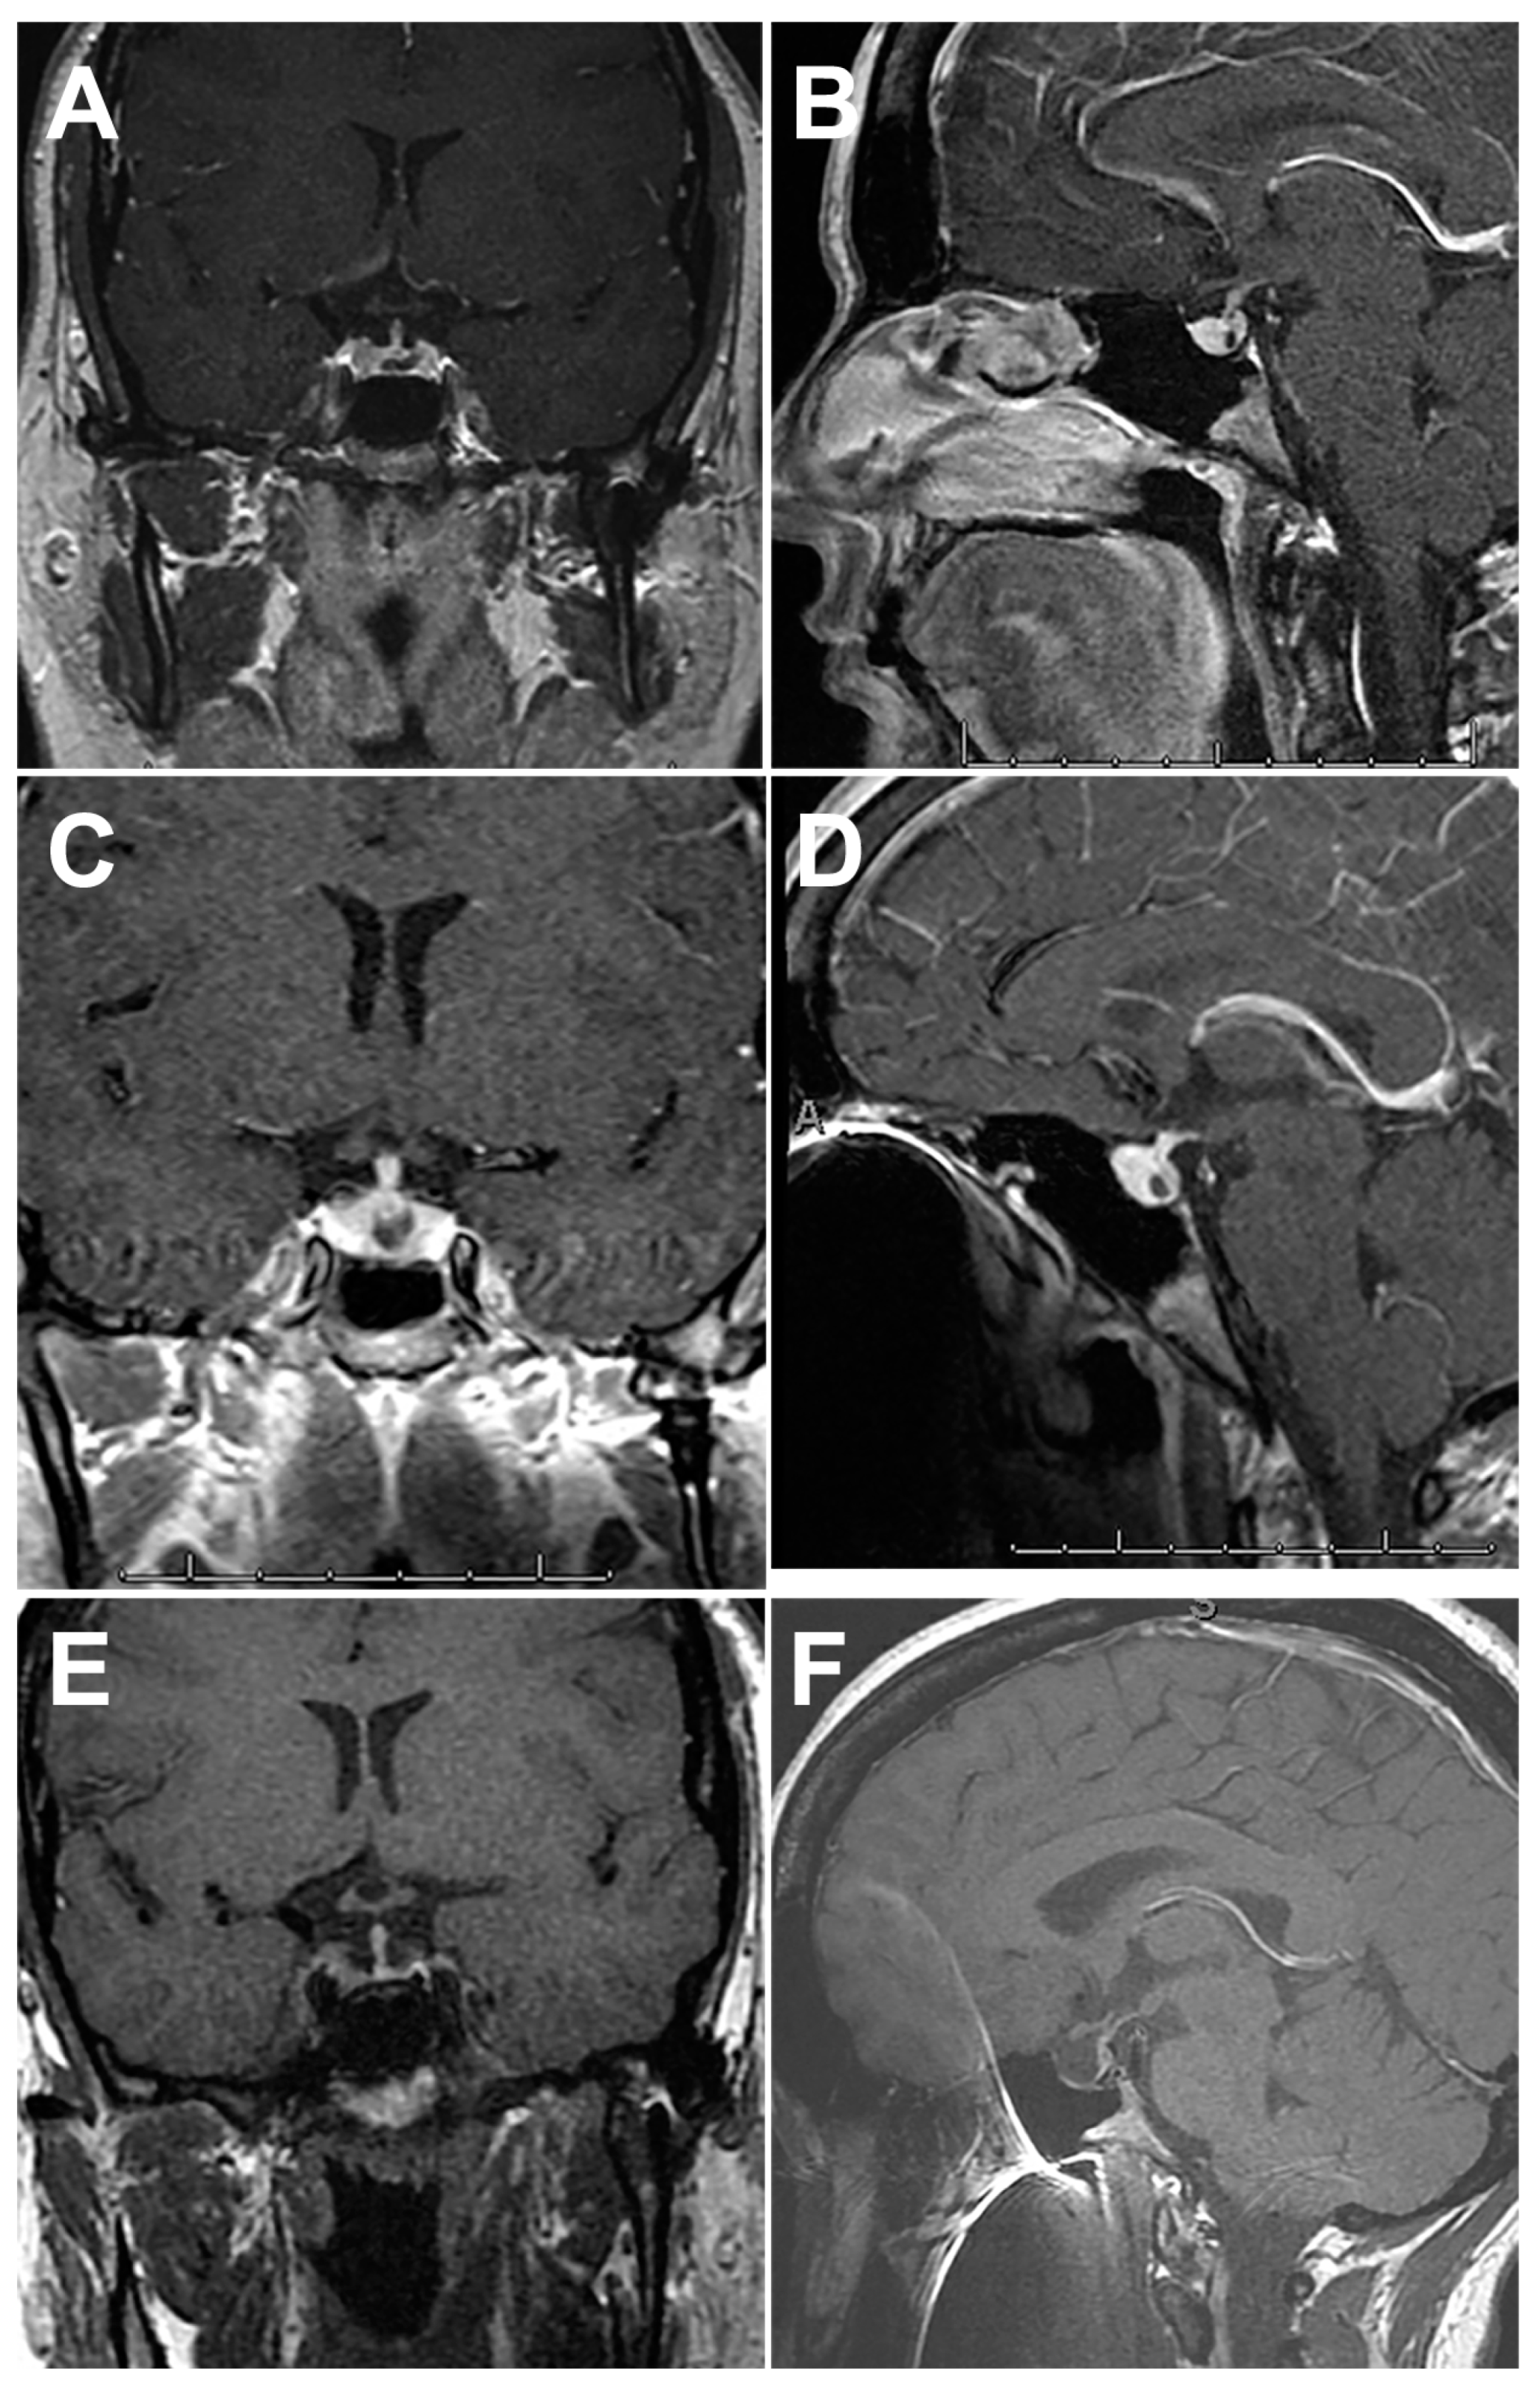

4.1. Imaging Features